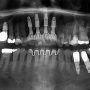

3. Implante dentário

O tratamento para implante dentário consiste no posicionamento de uma estrutura feita de titânio que funciona como uma raiz do dente. É uma cirurgia que permite ao cirurgião-dentista montar dentes ou pontes substitutas. Diferente das próteses dentárias (dentaduras), os implantes não se soltam, beneficiando a saúde bucal como um todo.

Recuperar o sorriso não é o único benefício da técnica, uma vez que a falta de dentes compromete a mastigação, fala, movimentos de abrir e fechar da boca. Por essas e outras razões, a recolocação dos dentes é indispensável e vai além de um sorriso bonito.